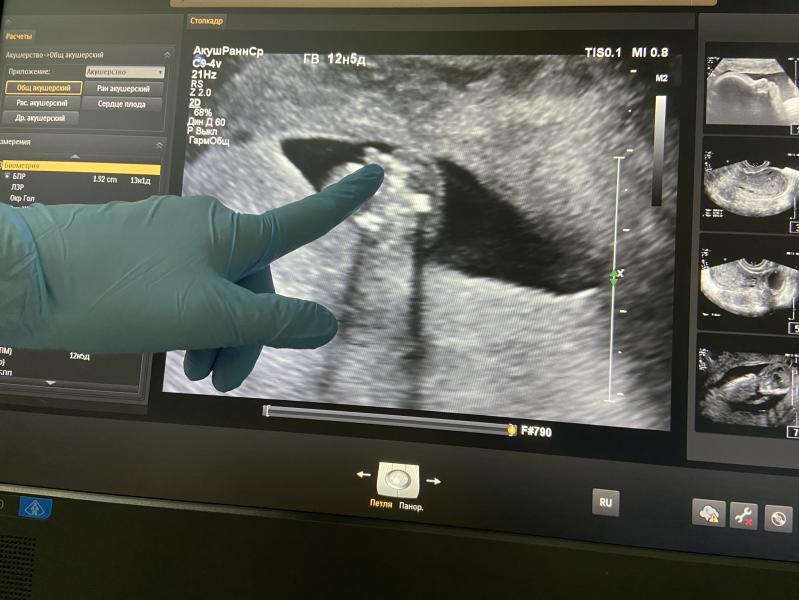

Вчера была на первом скрининге ,вот такой прекрасный малыш у меня сидит 😍 а на втором фото , это она мне показывала что у меня мальчик, он завернул ножки , а это получается вид с попы😅

Врач конечно предупредила что это может нас обманули и на 20 недели уже точно буду знать 😇